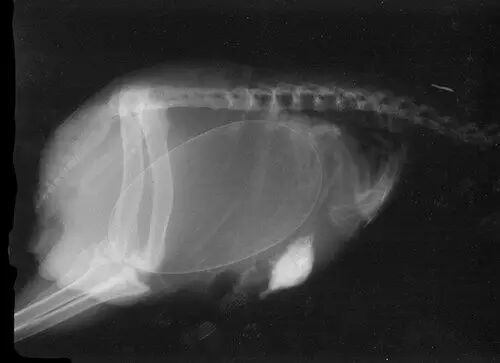

怀孕是一件神圣而又带有神秘色彩的事,她预示着新生命的来临。在动物世界,怀孕是怎样的一种奇迹,以下 14 种动物在怀孕期间的 X 线图片,我们可以通过全新的影像视角探查一番。

• 荷兰猪